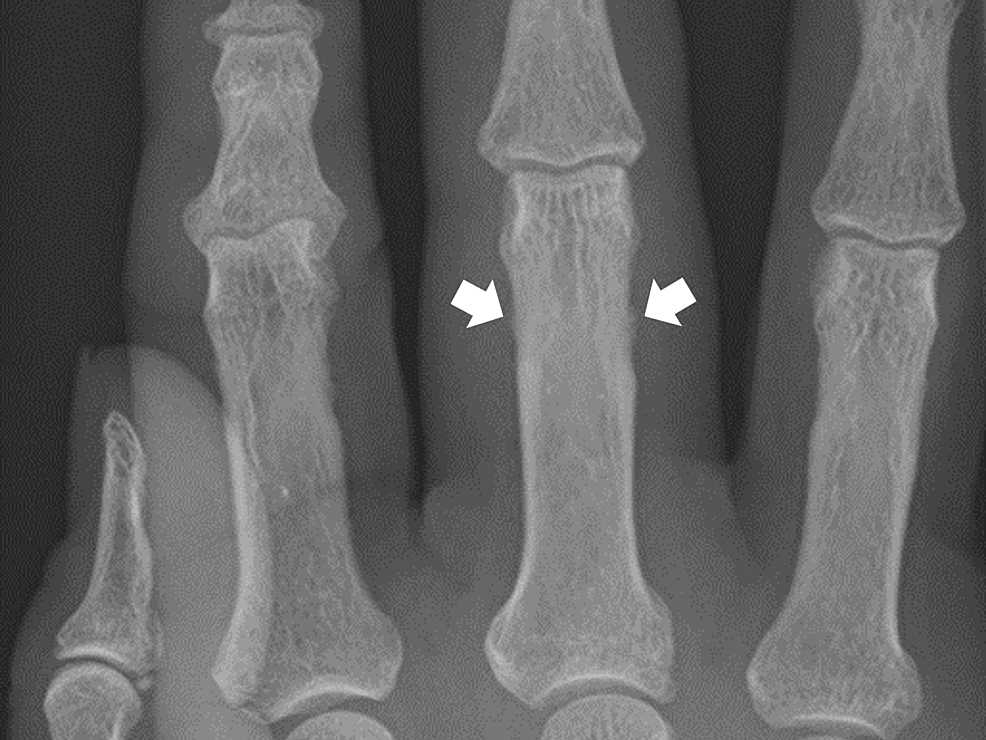

Septic arthritis proximal interphalangeal joint Image

Septic arthritis proximal interphalangeal joint Image Septic Arthritis Dip Joint septic arthritis of the hand is a serious disease that often results in dysfunction of the joint or even the need to. arthritis of the dip and pip joints are very common forms of osteoarthritis seen in the hand and can be associated with pain and deformity. this clinical guideline is intended for use by orthopedic surgeons. Septic Arthritis Dip Joint.

Figure2.Radiographic changes in the proximal interphalangeal (PIP Septic Arthritis Dip Joint Symptoms include intense pain, swelling and. septic arthritis should be considered in adults presenting with acute monoarticular arthritis. septic arthritis is a rare and serious condition that affects one or more of your joints. septic arthritis is a painful infection in a joint that can come from germs that travel through your bloodstream from. this clinical. Septic Arthritis Dip Joint.